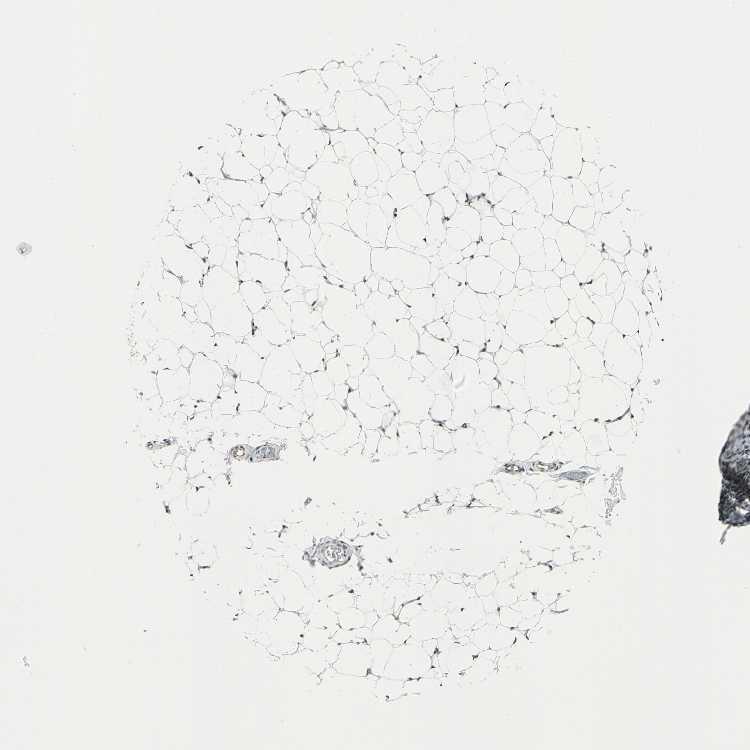

ADIPOSE TISSUE - Antibody stainingi

Antibody staining in the annotated cell types in the current human tissue is reported as not detected, low, medium, or high, based on conventional immunohistochemistry profiling in selected tissues. This score is based on the combination of the staining intensity and fraction of stained cells.

Each image is clickable and will lead to virtual microscopy that enables deeper exploration of all samples and also displays staining intensity scores, fraction scores and subcellular localization as well as patient and tissue information for each sample.

Antibody HPA006313

Adipocytes Not detected